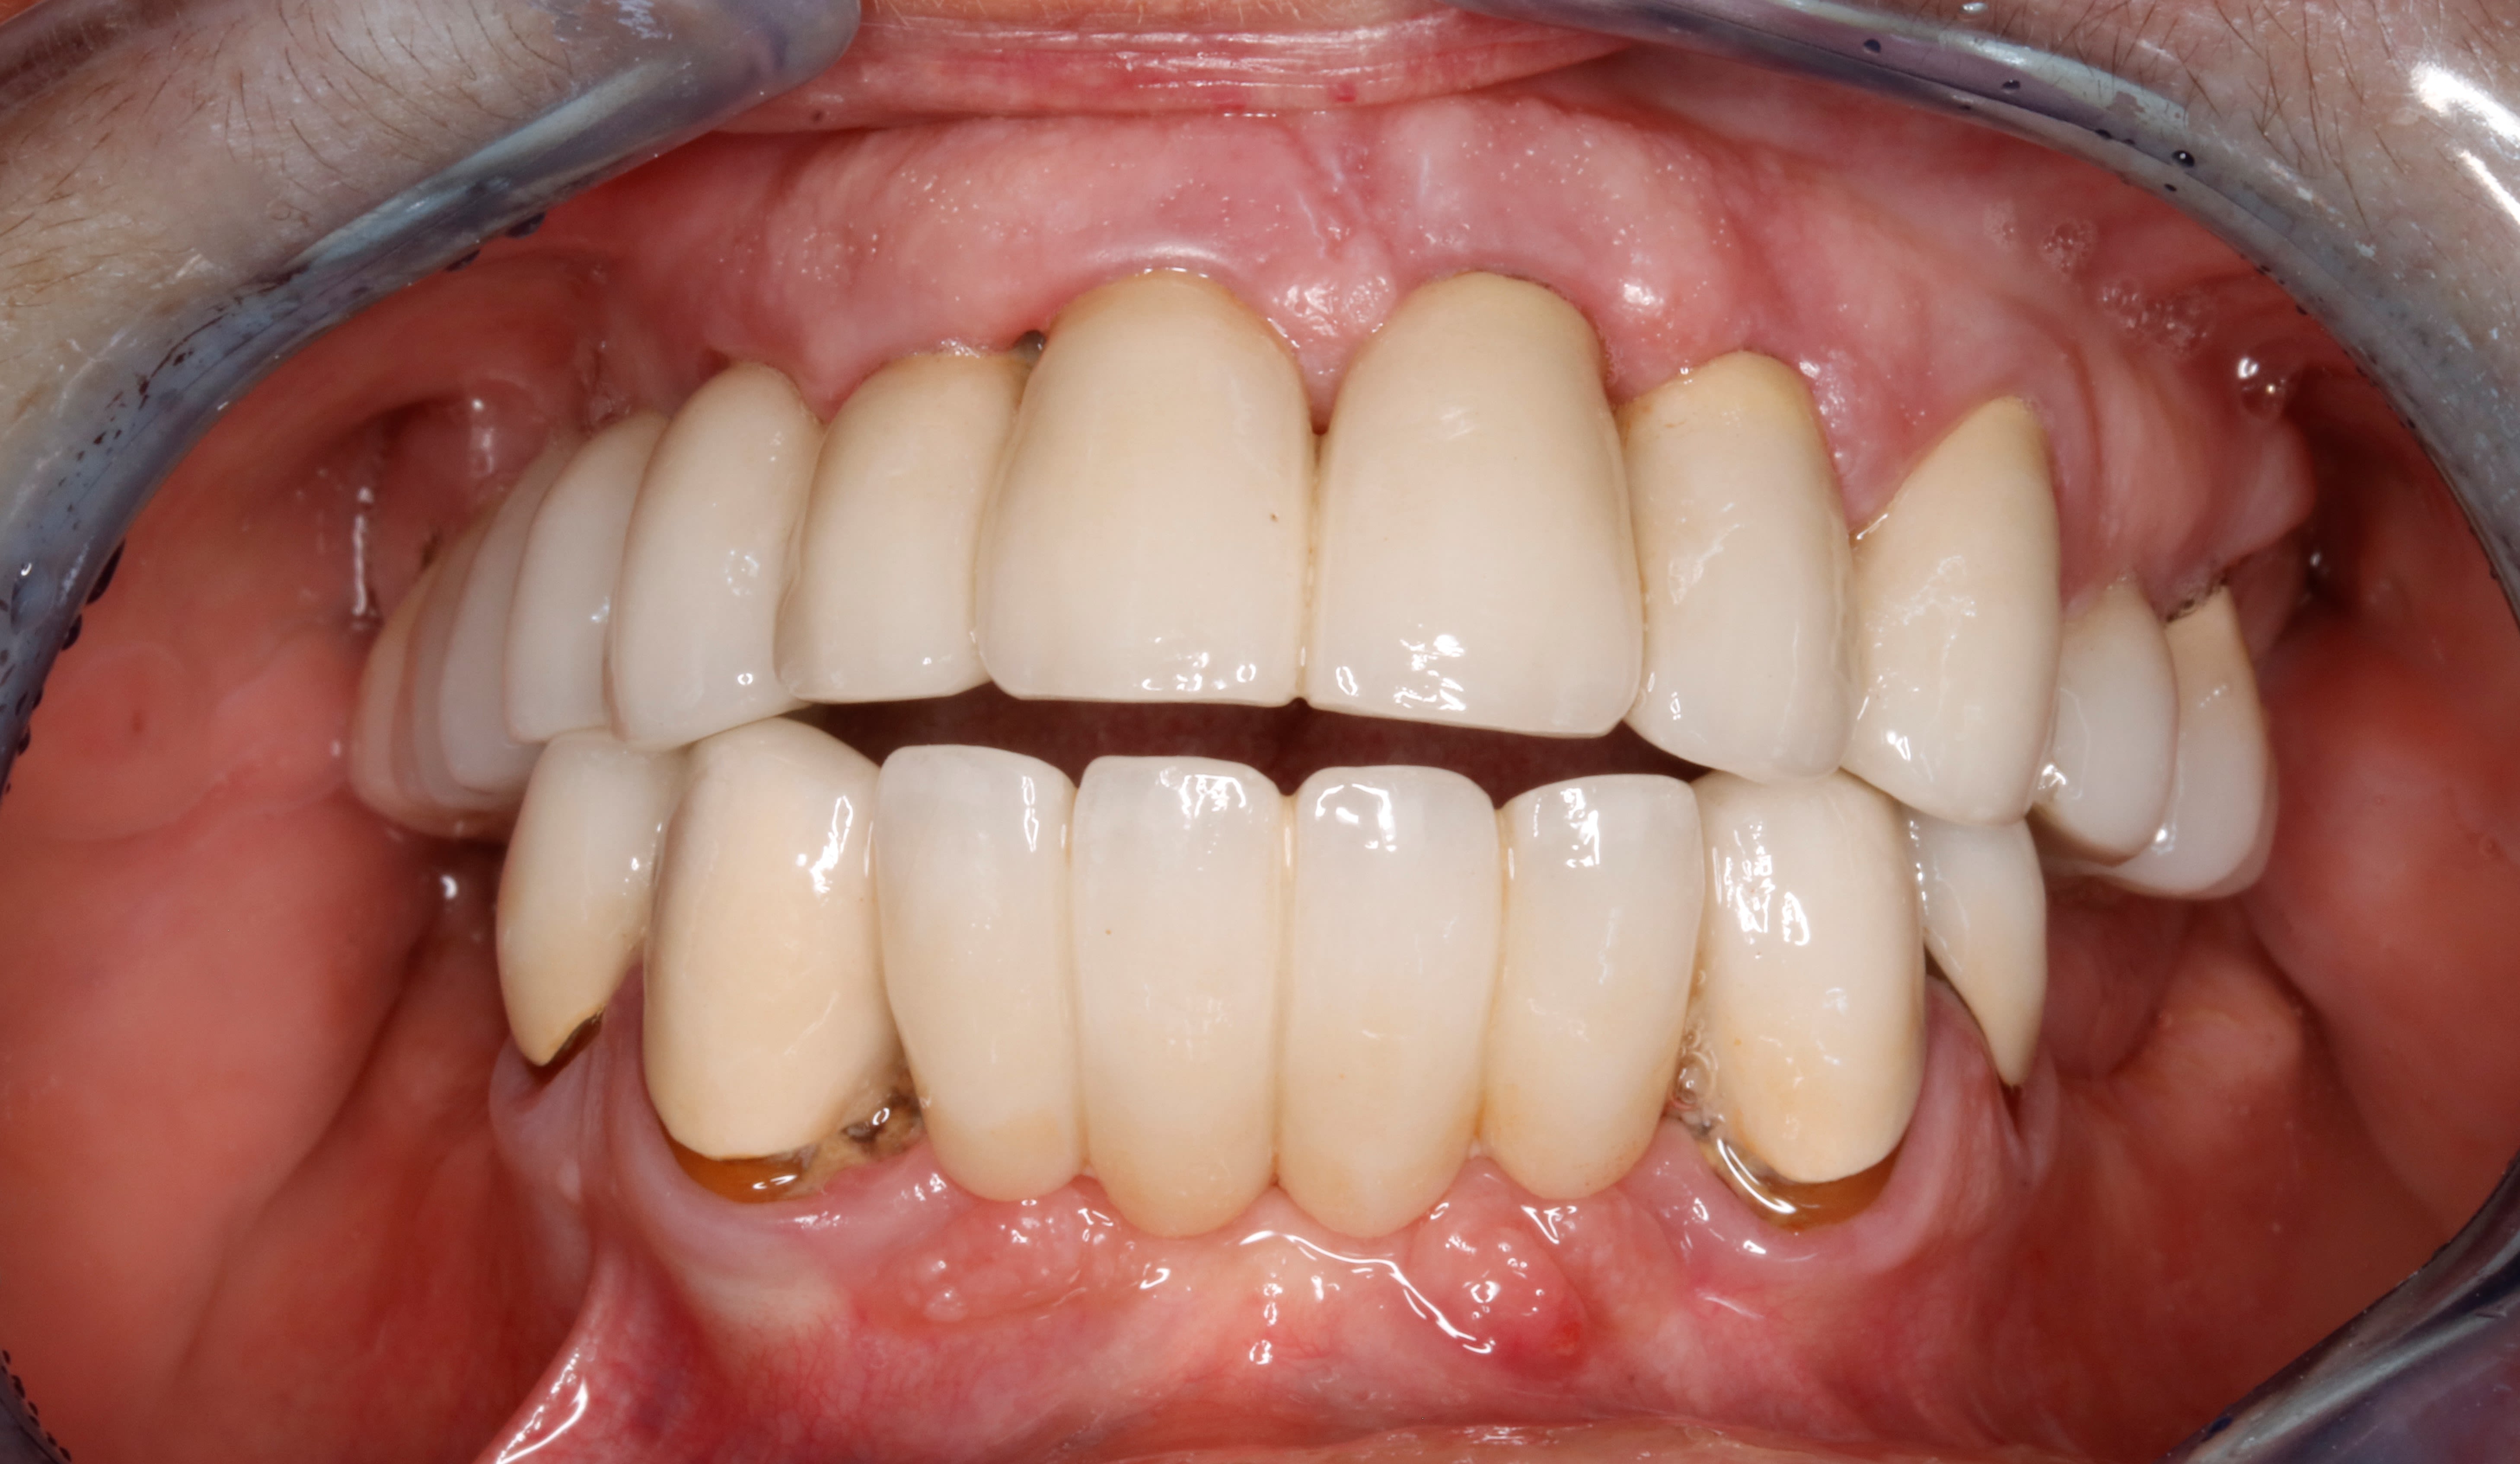

comme vous avez étés tres sage , j ai convoqué le cas de la béance

donc 10 ans après on en est là .

vises un peu les masséters puissants .

on s en sort bien .

de face .

hummmm d un point de vue paro , j aurais peut etre du extraire la 12

mais sinon , globalement , vu d ou on est parti , et vu l hygiène de vie et hygiène tout court ,

10 ans apres on s en sort bien !

petites caries sous 33 et 43 à machiner